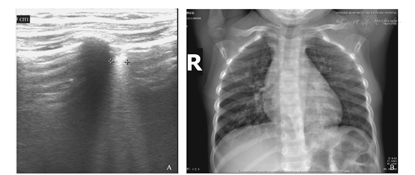

A.肺部超声可见双肺内多处胸膜线增厚,可见多条融合B线及多个大小不等的斑片状弱回声区,后下肺内融合B线,呈瀑布样。弱回声区,形态不规则,可见支气管充气征。B.X线胸片可见双肺纹影及肺门影稍紊乱、模糊,肺野内中带分布斑点、条絮状模糊影。

A.治疗6 d后肺部超声可见双下肺局部胸膜线模糊,A-线出现,右下肺散在B-线,其余区域未见异常;B.治疗6 d后X线胸片可见双肺纹理稍粗多、模糊,肺野内见少许条絮状,肺炎炎症大部分吸收。